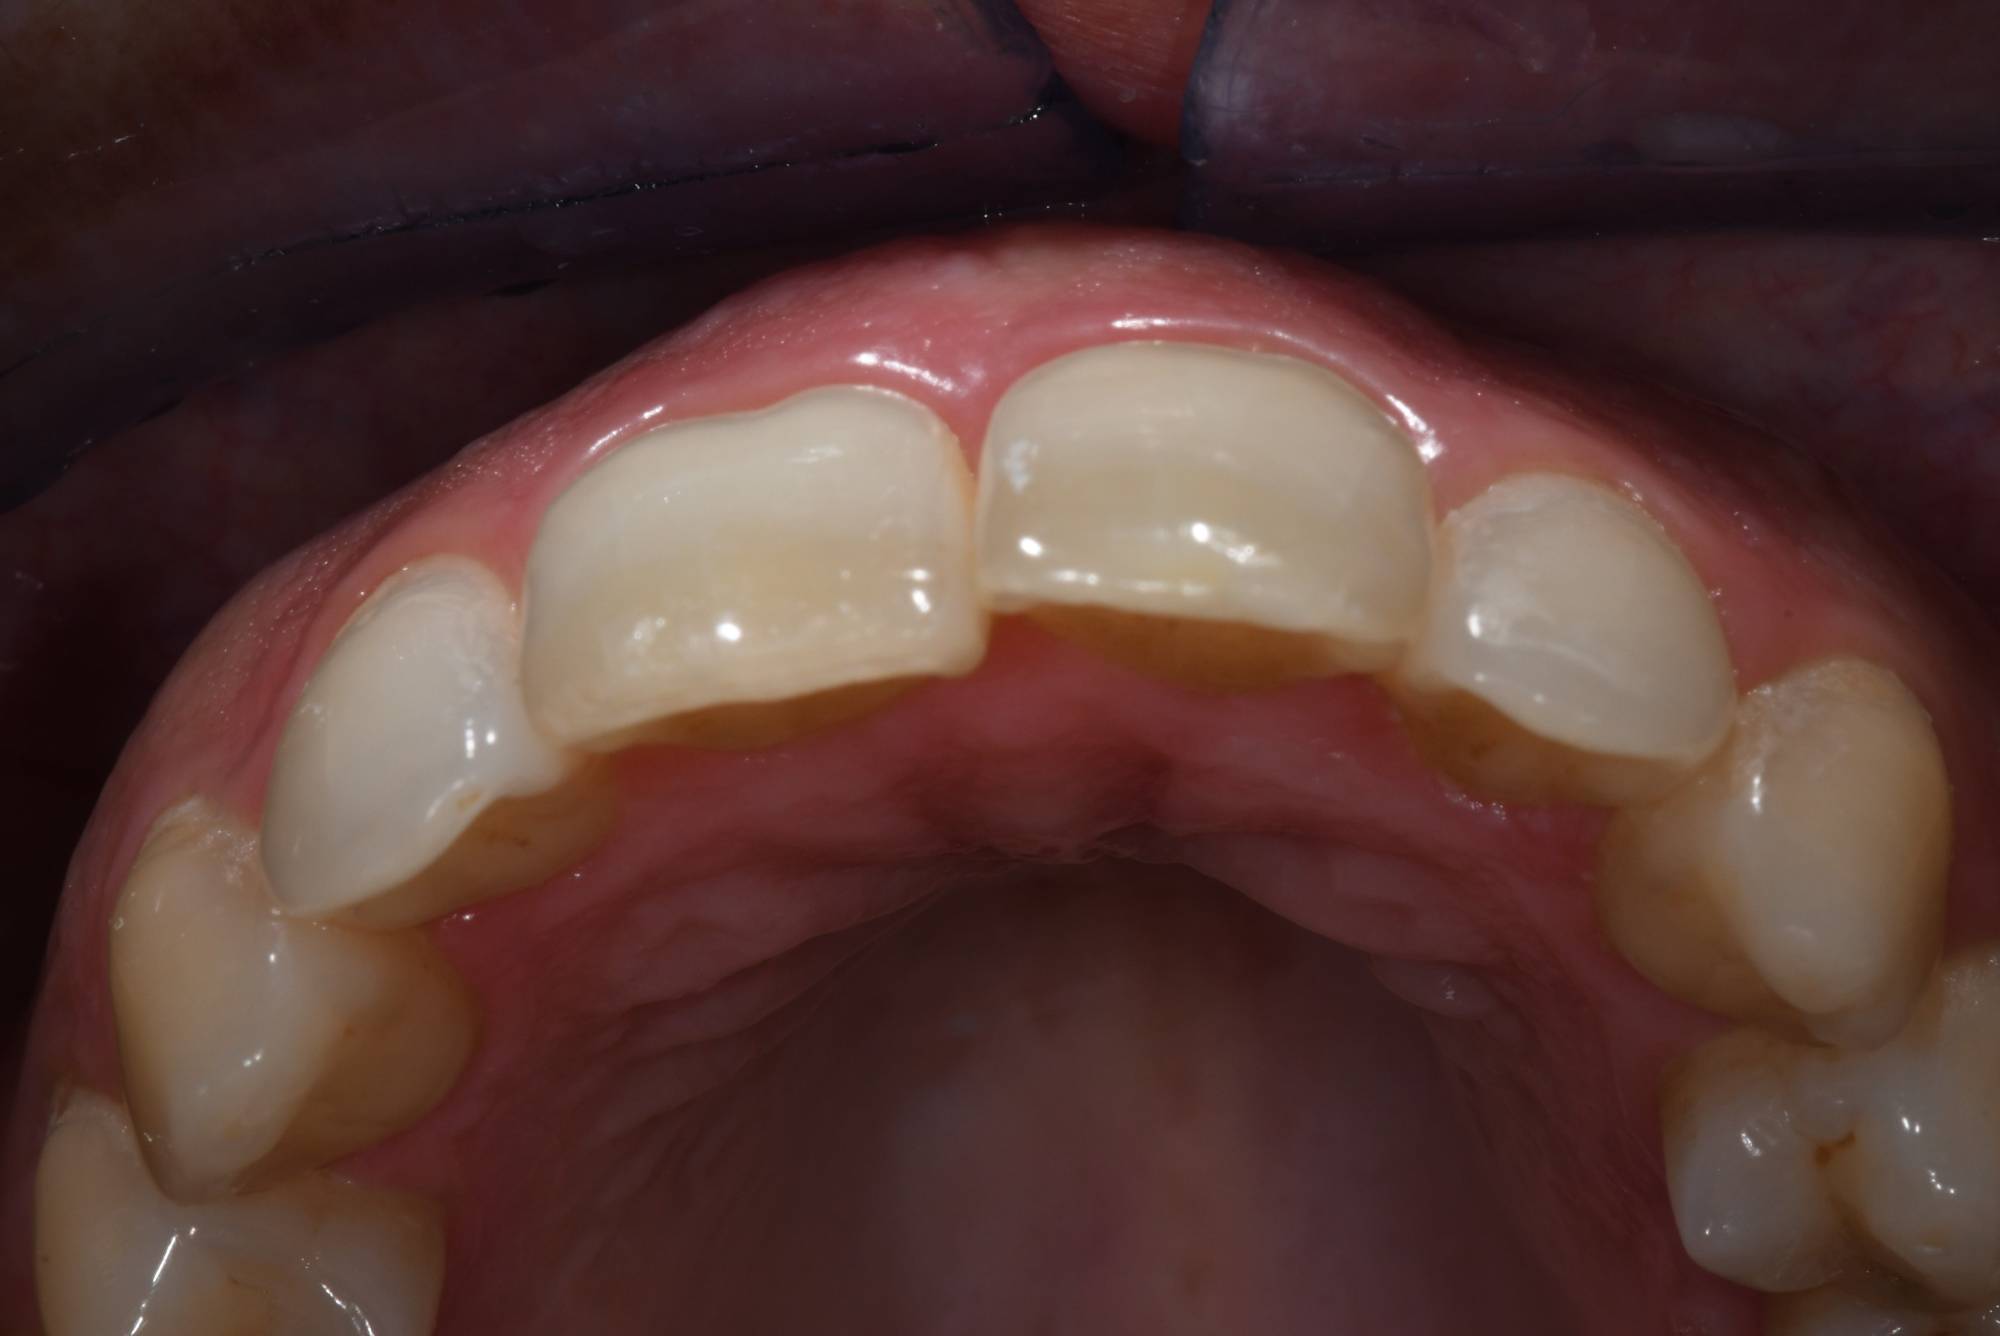

La buona notizia è che puoi tornare a sorridere con gli allineatori trasparenti! Guarda le foto qui sotto: la signora aveva un incisivo che sporgeva talmente tanto che non poteva chiudere le labbra e si vergognava di sorridere. Viveva quel dente in fuori come una deformità, ma non voleva mettere l’apparecchio tradizionale, si riteneva troppo “vecchia”.

Fortunatamente esiste questa nuova tecnologia che le ha permesso di allineare i suoi incisivi, come vedi nella seconda foto, senza apparecchio fisso e in tempi rapidi.